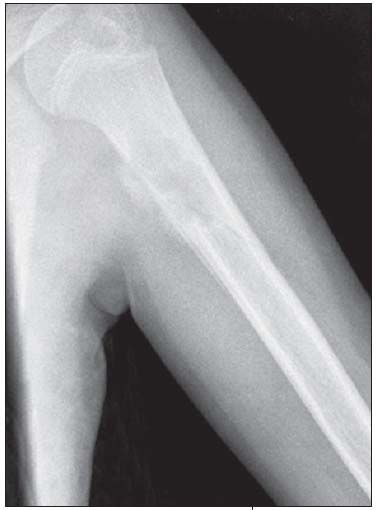

Anteroposterior and lateral views of the patient's left humerus were ordered.

The radiographs show a centrally placed lytic lesion with lobulated contours and a well-defined transition zone in the proximal shaft of the humerus. An oblique pathological fracture runs through the cyst No other lesions are visible. A thick periosteal reaction on the medial aspect of the lytic lesion is also present; the periosteal reaction is atypical in this case; however, the radiographs were obtained 10 days after the fall.

This is a unicameral, or simple, bone cyst. Many of the lesions in the differential diagnosis, including aneurysmal bone cyst, osteomyelitis, malignant lytic lesion (such as eosinophilic granuloma or bone metastasis), can be excluded on the basis of location. The location of simple bone cysts is usually the humeral head, ball of the foot, proximal femur, or proximal humerus or calcaneus.

A simple bone cyst may be an incidental finding. However, like this child, most patients present with a pathological fracture. The pathognomonic sign after a fracture is a fallen fragment in the most dependent portion of the cyst. Occasionally, a periosteal reaction can be seen. A simple bone cyst is a fluid-filled cavity lined with fibrous tissue. It is thought to result from venous outflow obstruction, which leads to an increased intraosseous pressure and a consequent stimulation of

osteoclastic activity. This benign lesion usually devel-ops within the first 2 decades of life. The cyst causes bone instability and sometimes may be associated with pathological fractures after relatively minor trauma.